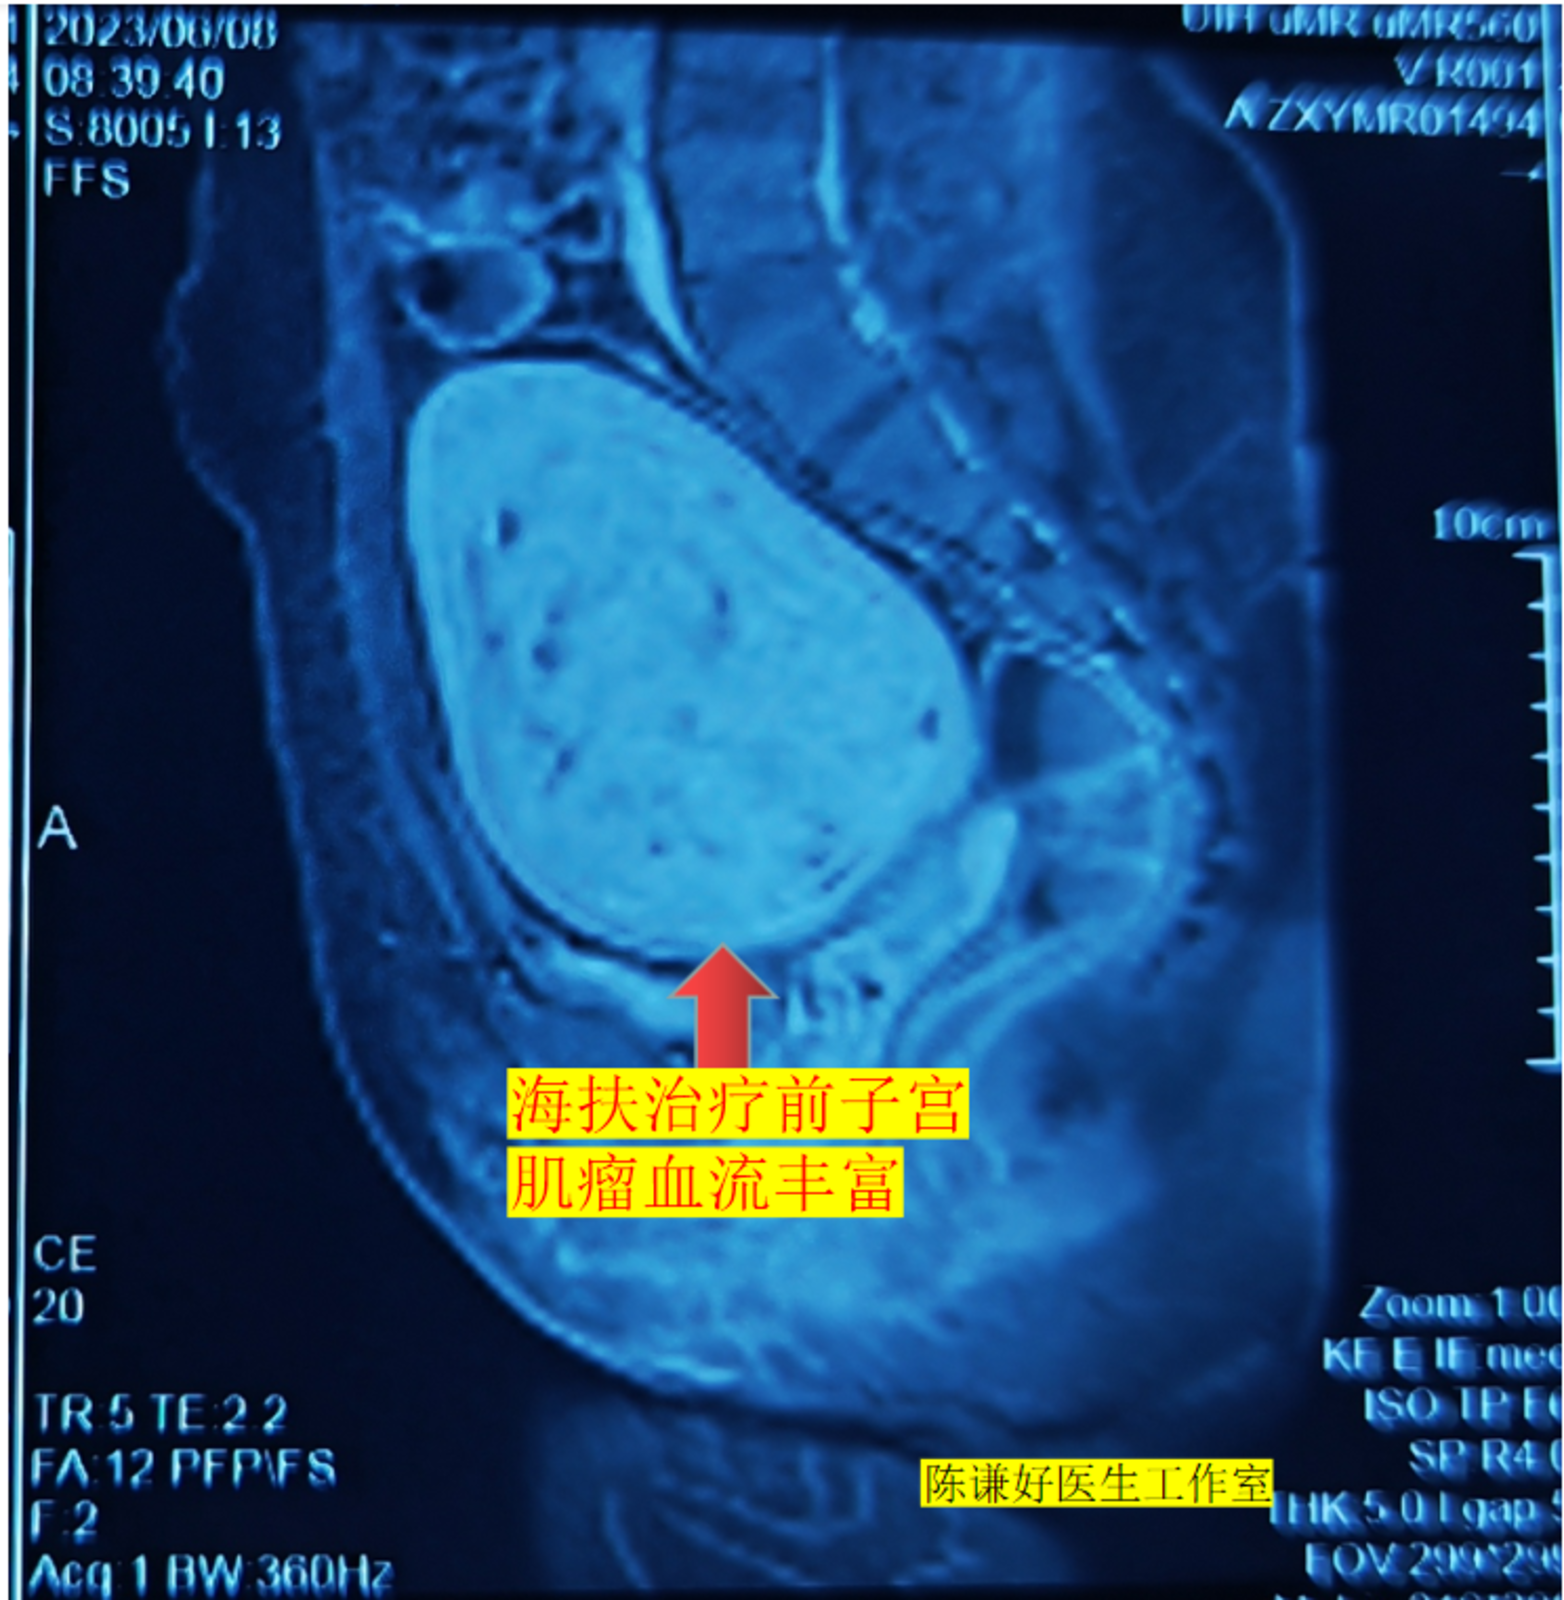

9.5厘米子宫肌瘤海扶刀治疗病例

患者在2018年发现子宫肌瘤,当时肌瘤有6cm,没有及时进一步治疗,之后肌瘤逐渐增大,现在肌瘤增大到9.5cm,同时伴有月经量增多,严重贫血。

患者不愿意选择传统手术,在了解到海扶刀可以无创的治疗子宫肌瘤后,专门从天津至我们中心进行治疗,不到40分钟肌瘤就完全消融,患者今天复查显示肌瘤消融满意,病人今天下午就正常回家了。